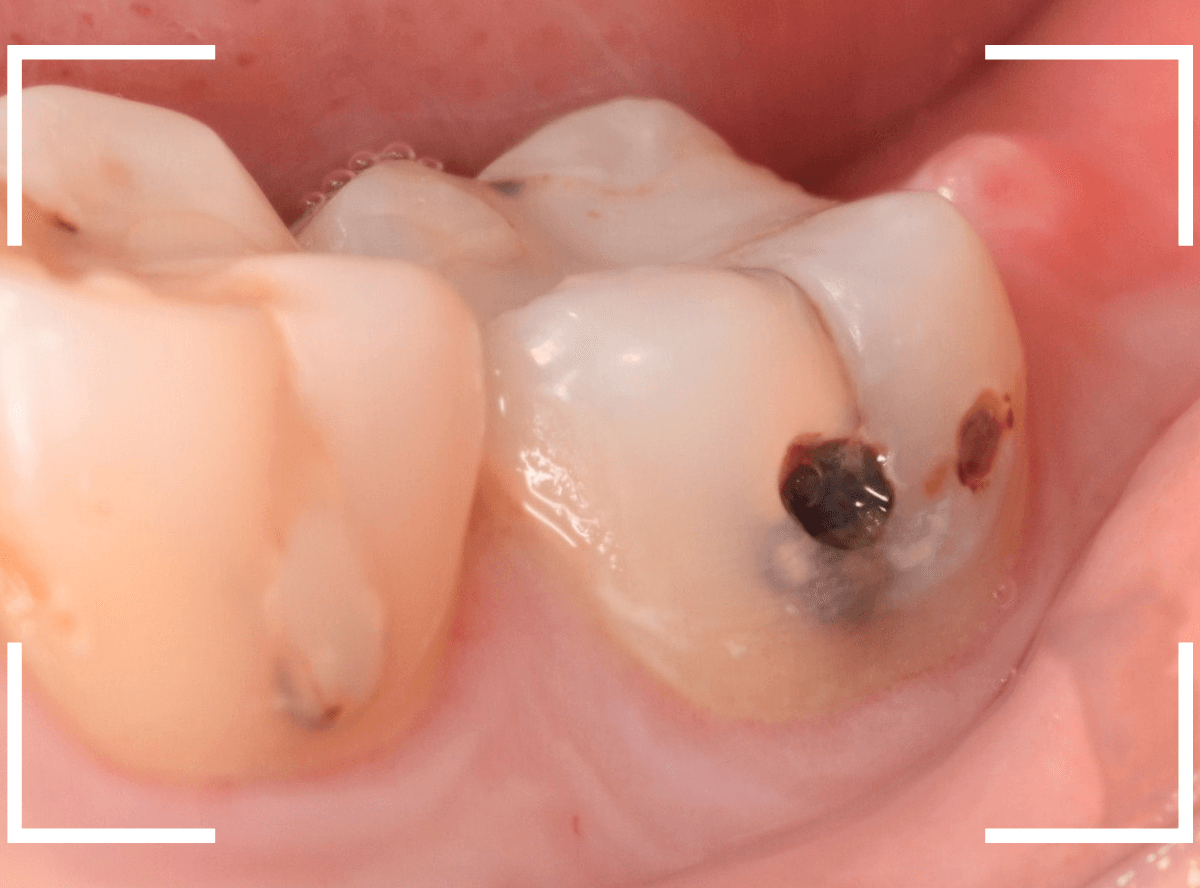

Case.9 レントゲン写真で写らない側面の虫歯

歯の側面が大きな虫歯になってしまった患者さんのケースです。

このように歯の側面が虫歯になった場合、レントゲン写真で虫歯の状況がはっきりわからない事が多いです。

レントゲン写真では、あまり大きな虫歯のようには見えません。

治療を開始します。

歯を少し削ると、すぐに大きな虫歯の穴が出てきました。

さらに虫歯を削ります。

神経に触れてしまいそうなほど、深くて広い虫歯ですね。

全ての虫歯を除去したところです。

何とか神経に触れる寸前のところで踏みとどまれましたが、レントゲン写真からは想像できない虫歯の深さでした。